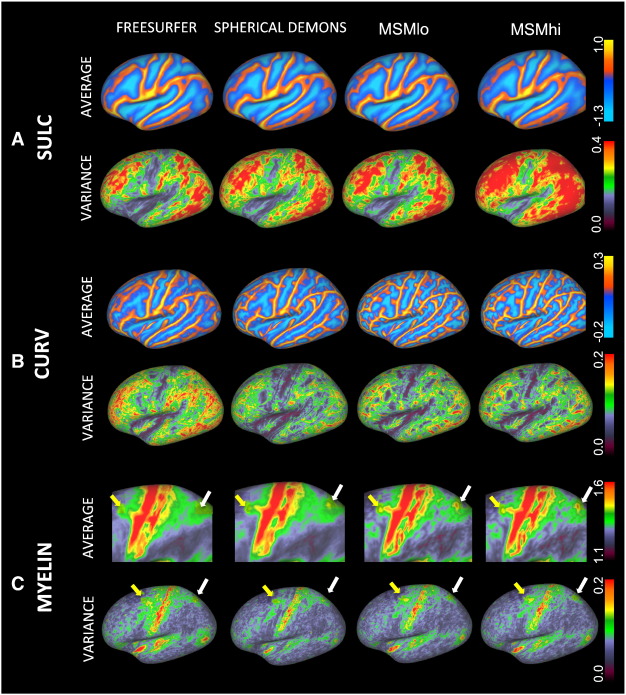

Compute a transformation of

2D/3D space

based on a single feature (e.g. image gray value),

or a low-dimensional feature vector (e.g. sulcal depth, curvature, myelin)

from Yeo, et al., Journal of Neurophysiology, 2011 and Robinson et al., NeuroImage, 2014